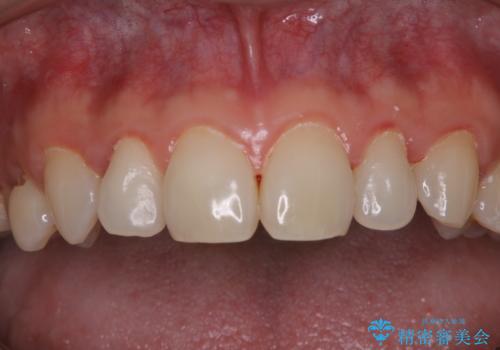

開始前

- 40年ほど歯科医院へ行ってなく、ザラつきがきになるとの事で来院されました。最近は普段の歯磨きの際、出血することがあり、歯ブラシ指導も希望されました。

お口全体に、歯垢・歯石が付着していたため、自費クリーニング(PMTC)60分コースを行い、徹底的に除去しました。